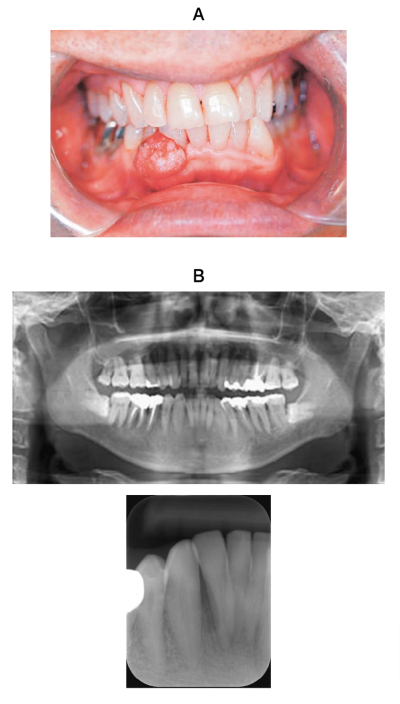

111B

67 歳の男性。下顎前歯部歯肉の腫脹を主訴として来院した。1か月前に気付き、徐々に大きくなってきたという。オトガイ部の感覚に異常はなく、顎下リンパ節とオトガイ下リンパ節の腫脹もない。初診時の口腔内写真、エックス線画像及び生検時の H-E 染色病理組織像を別に示す。

適切な治療法はどれか。1つ選べ。

a. 歯肉切除

b. 32⏋の抜歯

c. 下顎辺縁切除

d. 下顎区域切除

e. 放射線治療

c. 下顎辺縁切